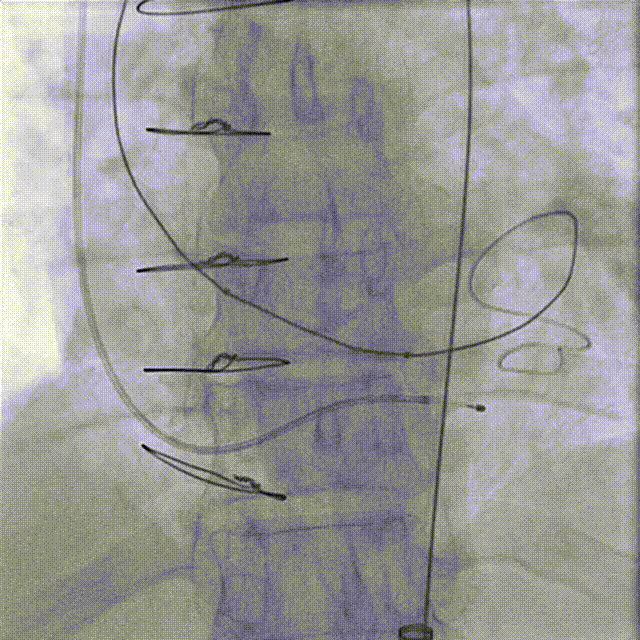

CT评估(TAVR术后):

1.CT评估(多平面测量)

TAVR瓣架低端为基准,测量瓣架上的2,4,6,8mm层面,直径都在22-23mm左右,原TAVR瓣架呈直筒状。